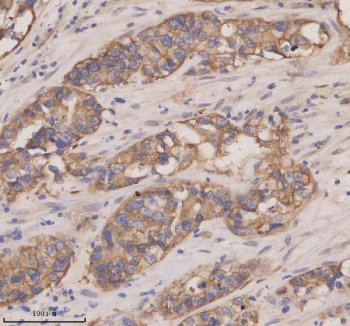

Immunohistochemical staining of CXCL13 using anti-CXCL13 antibody. CXCL13 was detected in a paraffin-embedded section of human appendiceal adenocarcinoma tissue. Heat mediated antigen retrieval was performed in EDTA buffer (pH 8.0, epitope retrieval solution). The tissue section was blocked with 10% goat serum. The tissue section was then incubated with 2 ug/ml rabbit anti-CXCL13 antibody overnight at 4oC. Peroxidase Conjugated Goat Anti-rabbit IgG was used as secondary antibody and incubated for 30 minutes at 37oC. The tissue section was developed using an HRP secondary and DAB substrate.